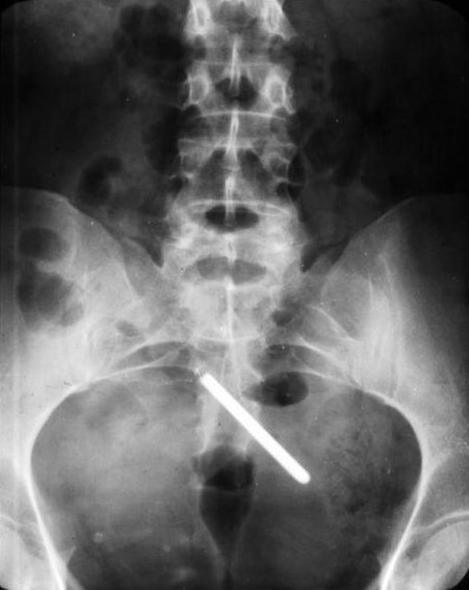

Термометр